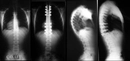

Fizik Tedavi ve Egzersiz: Fizik tedavi, skolyozun ilerlemesini durdurmak ve postürü düzeltmek için önemli bir rol oynar. Hastalara özel egzersiz programları uygulanır. Bu programlar, kas gücünü artırmayı ve esnekliği geliştirmeyi hedefler. Ortez Kullanımı: Ortezler, omurganın düzeltilmesine yardımcı olmak için kullanılan cihazlardır. Özellikle büyüme çağındaki çocuklar için etkili olabilir. Ortezlerin kullanım süresi, skolyozun şiddetine bağlı olarak değişir. Cerrahi Müdahale: Eğer skolyoz ilerliyorsa ve diğer tedavi yöntemleri yeterli olmuyorsa cerrahi müdahale gerekebilir. Cerrahi işlemler genellikle omurganın düzeltilmesi ve stabilizasyonunu hedefler. Bu tür bir müdahale, hastanın yaşına, genel sağlık durumuna ve skolyozun şiddetine göre planlanır. SonuçSkolyoz tedavisi, bireysel ihtiyaçlara göre özelleştirilmelidir. Tedavi yöntemleri arasında fizik tedavi, ortez kullanımı ve cerrahi müdahale gibi seçenekler bulunmaktadır. Erken tanı ve uygun tedavi, skolyozun yönetiminde kritik öneme sahiptir. Her birey için en uygun tedavi yönteminin belirlenmesi, uzman bir hekim tarafından yapılmalıdır. Ek BilgilerSkolyoz hastalarının takip edilmesi ve düzenli kontrollerin yapılması, tedavi sürecinin etkinliği açısından önemlidir. Ayrıca, skolyozun psikolojik etkileri de göz önünde bulundurulmalıdır. Hastaların duygusal destek alması, tedavi sürecini olumlu yönde etkileyebilir. Skolyoz ile ilgili daha fazla bilgi ve destek almak için uzman sağlık profesyonellerine başvurulması önerilmektedir. |